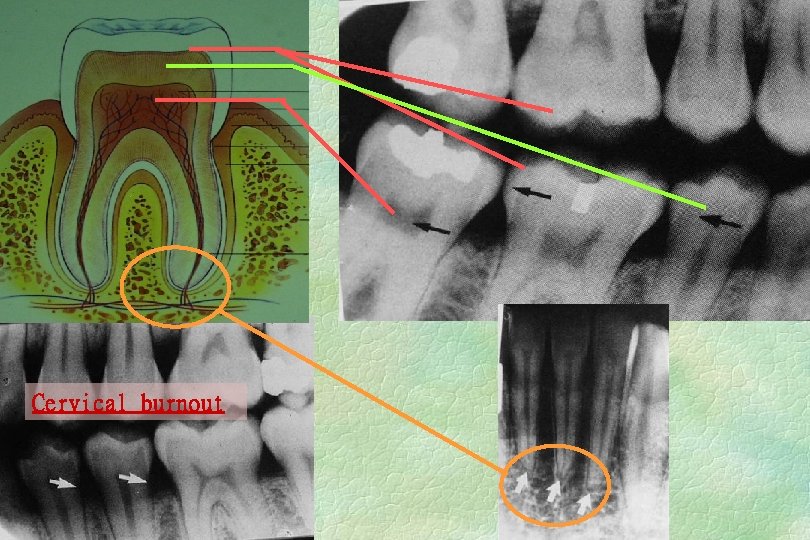

Cervical burnout

Normal Radiographic Anatomy TEETH u u u Enamel, dentin, cementum, Pulp, root canal Enamelodentin junction C-E junction Normal and developing WWC

Normal Radiographic Anatomy Periodontal ligament space u u u R-L (radiolucent) space between root & lamina dura Width of PDL varied by individual, teeth & location; thinner in the middle of the root, slightly widened near the alveolar crest & apex …. fulcrum of physio logical movement of a tooth Double PDL space. . . created by the shape of the tooth. WWC